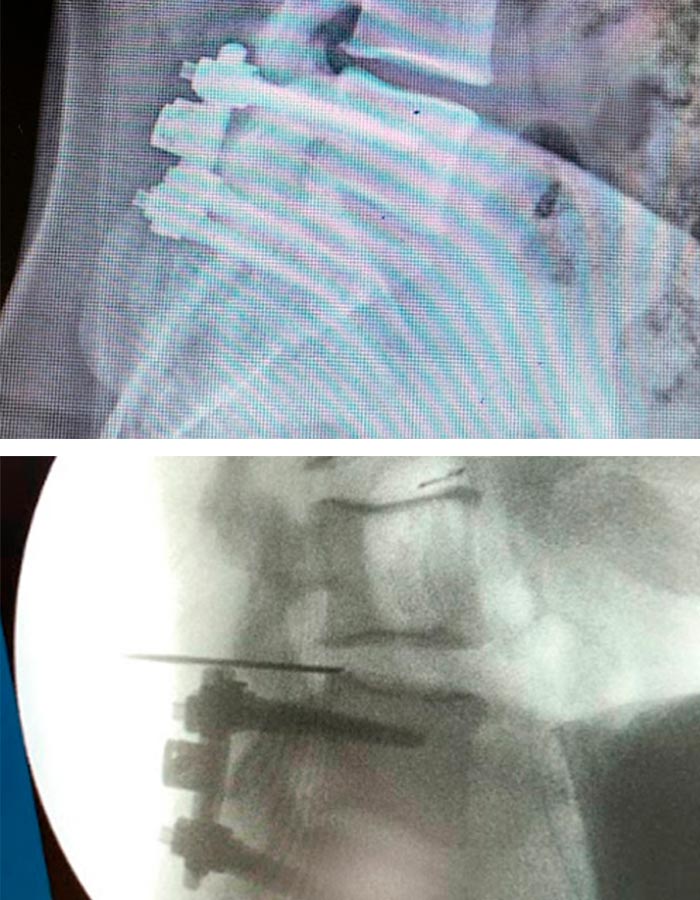

La cirugía mínimamente invasiva de endoscopia de avanzada de columna se lleva a cabo en unas dos horas a través de un portal de unos 3mm, situado en la parte posterior de la columna :

1. Se introduce una aguja guía que nos ayudará a introducir un dilatador para acceder a la zona de trabajo sin dañar ningún tipo de tejido.

2. Una vez localizado el nivel y visualizado el disco procedemos a extraer la hernia muy despacio para que no se desprendan nuevos trozos.

3. Se revisa bien la zona y se retira un nuevo trozo alojado detrás del primero.

4. Cuando ya se ha retirado toda la hernia debemos limpiar ambos lados de la vértebra para asegurarnos de que el canal está limpio y el tejido neurológico tiene el espacio correcto y está completamente liberado.

5. Por último, cauterizamos bien la zona que rodeaba al fragmento extraído.

6. Se realiza una infiltración con corticoides locales.